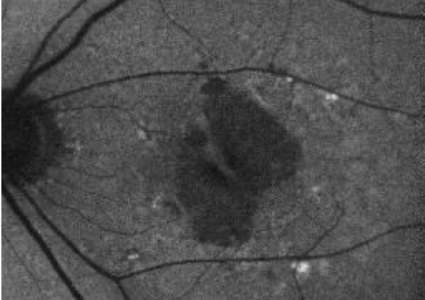

Baseline

BCVA: 6/7.5

Choroidal hypertransmission defect is a sign of atrophy.